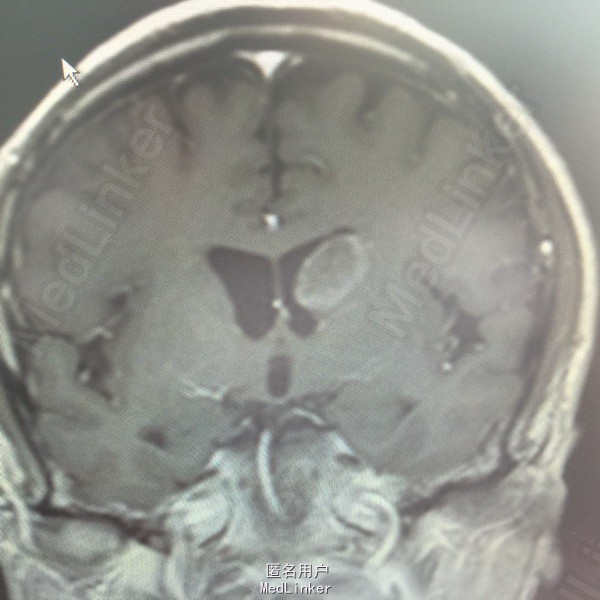

男,54岁,以头痛半个月入院。 现病史:半个月前无诱因头痛,呈胀痛,无呕吐,无意识障碍,病来咳嗽、咳痰,体重减轻约5斤,无发热。 既往史:无特殊。

查体:BP:150/100mmHg,神清语明,两瞳孔等大正圆,直径约3.0mm,光敏,四肢肌力5级,肌张力正常,腱反射艹,左侧共济运动阳性,病理征阳性,脑膜刺激征(-)。 辅查:见下:

肺癌脑转移。 影像解读(影像如何解读是临床工作中非常重要的一环)。 左侧额叶近皮质长Tl长T2信号,局部颅骨缺损,右侧枕叶不规则病灶,TlWl呈中心呈等信号,周围高信号,T2Wl呈高低混杂信号,伴大片水肿,相邻侧脑室后角、胼胝体受压。增强呈不规则环环强化。 已进行局部放疗治疗。